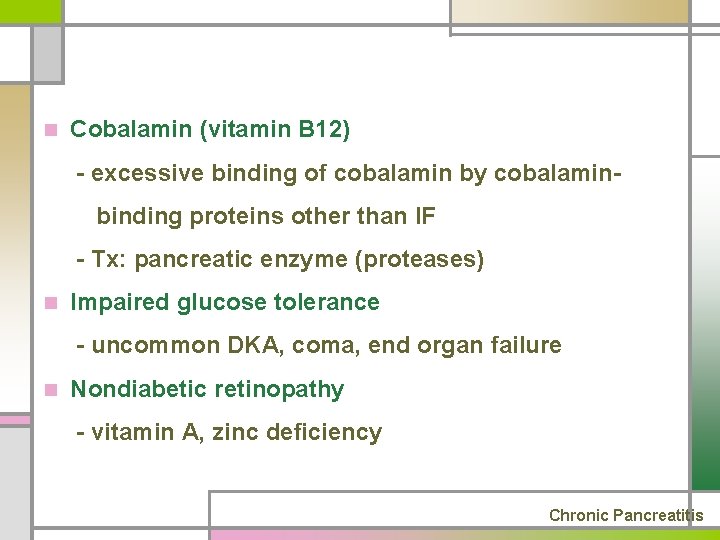

n Cobalamin (vitamin B 12) - excessive binding of cobalamin by cobalaminbinding proteins other than IF - Tx: pancreatic enzyme (proteases) n Impaired glucose tolerance - uncommon DKA, coma, end organ failure n Nondiabetic retinopathy - vitamin A, zinc deficiency Chronic Pancreatitis